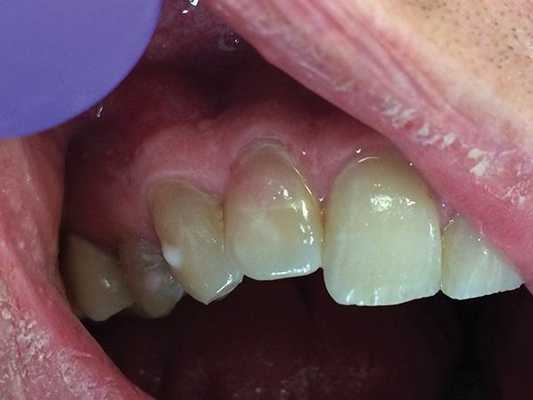

В исследование были включены 25 пациентов с диагнозом локальной рецессии, с клинической картиной, при которой отмечалась рецессия только у одного из идентичных зубов (рис. 1). Рис. 1. Исследование проводили у каждого пациента в области идентичных зубов. В данном случае: зуб 1.3 с рецессией, 2.3 — без рецессии. Исследовали 30 зубов, имеющих рецессию от 1,0 до 4,8 мм. Контрольная группа включала в себя 30 идентичных зубов с противоположной стороны, не имеющих рецессии (6 зубов имели минимальную потерю прикрепления — до 0,5 мм). Возраст пациентов составлял от 21 года до 36 лет, среди них было 13 женщин и 12 мужчин.

Иногда поражение проявляется клинически очевидным образом. На фото 7-10 представлен случай, когда пациент сам отметил розовую дисколорацию в пришеечном отделе правого бокового резца. Хотя чувствительность пульпы была нормальной, было обнаружено перфорирующее поражение вдоль дистально-щечной стороны зуба. Хотя предварительно считалось, что наличие розовых дисколораций свидетельствует о внутренней резорбции зуба, на самом деле в большинстве таких случаев клинически диагностируют ИПКР.

Фото 7. Случай ИПКР в области 10 зуба с формированием розовой дисколорации.